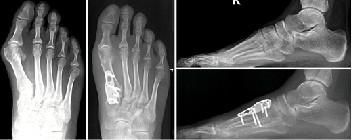

如果非手术治疗失败,可以考虑手术治疗。(证据级别:4)在选择手术前,必须确定拇外翻的严重程度。为了做到这一点,使用了负重平片射线照相术。

Lapidus关节融合术

当视察到严重的畸形时,这是另一种选择。通过切除内侧楔形关节软骨和第一跖骨基部,两者融合。用钢板或螺钉固定。